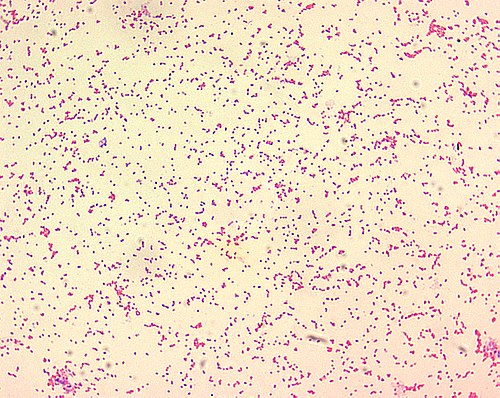

| Pôvodca: | gramnegatívne baktérie rodu Brucella |